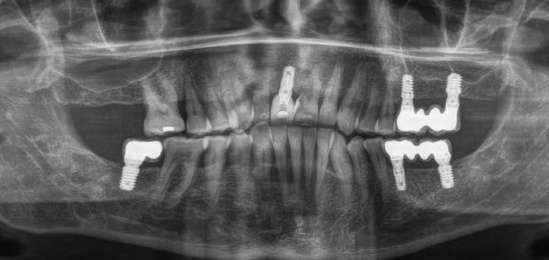

laterales se ponen de manifiesto aún más varias lesiones de esmalte que indican la parafunción en el paciente, unido a los desgastes excesivos en varias zonas (figuras 3 y 4). El paciente acude por dolor y movilidad en la pieza 11, que se ha incrementado en los últimos días, además de sensación de “diente crecido” que como podemos ver en las fotografías iniciales es real, ya que el diente se encuentra ligeramente extruido en relación con el contralateral. Estos signos parecen indicarnos una fractura o fisura. En la fotografía oclusal, podemos observar el desplazamiento del diente debido a la movilidad (figura 5). Posteriormente se realiza un sondaje positivo de la pieza, que lleva a 11 mm por lo que se confirma la sospecha de fractura y se procede a la exodoncia del diente, realizándose una regeneración posterior del alveolo con PRGF-Endoret y

esperándose 4 semanas hasta el cierre de los tejidos blandos y la neoformación ósea inicial para la colocación de un implante temprano. Cuatro semanas después, realizamos un cone-beam de control para conocer el estado del tejido óseo y poder planificar el implante. En el corte seccional observamos que se ha regenerado por completo el lecho receptor y tenemos un hueso óptimo para la inserción del implante, que por el tiempo transcurrido además es muy sencillo de expandir, con el propio implante generándose una expansión atraumática que nos permitirá ganar anchura ósea y con un implante estrecho de 3,5 mm de diámetro logramos posicionarlo sin dañar la desembocadura del nervio incisivo (figura 6). En cuanto a la longitud, con 7,5 es suficiente, no necesitándose un tamaño mayor para un correcto rendimiento biomecánico posterior.

Figura 6. Corte seccional de planificación del implante donde observamos el volumen óseo regenerado y la disposición del implante que se va a insertar por delante de la desembocadura del nervio incisivo.

El paciente continúa en seguimiento posterior, con revisiones cada 6 meses durante los dos primeros años. En todas ellas no existe complicación ni pérdida ósea asociada al implante, tal como podemos ver en la radiografía de control a los dos años (figura 18).

Cinco años después, llevamos a cabo un nuevo cone-beam y en el podemos observar la evolución del implante y de la sobre-corrección vestibular llevada a cabo en la cirugía inicial. Tanto el implante como el hueso que se ha formado a nivel vestibular fruto del injerto empleado está estable y se mantiene sin pérdida ósea asociada, tal como mostramos en los cortes del cone-beam

inicial y final a los 5 años de seguimiento (figura 19). En las imágenes intraorales tomadas en este punto del seguimiento se constata el éxito del tratamiento (figuras 20 y 21). En la radiografía periapical, observamos con mayor detalle la regeneración del tejido óseo del diente en posición 11 así como la estabilidad ósea del implante (figuras 22 y 23).

Figura 19. Imagen inicial del cone-beam y final con el implante cargado a los 5 años de seguimiento con la estabilidad del implante y del hueso generado mediante el injerto

Figuras 22 y 23. Radiografía periapical inicial y a los 5 años de seguimiento.